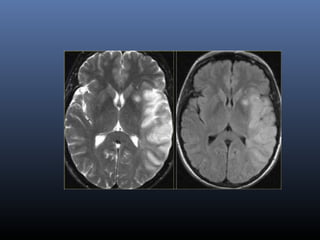

MRI in stroke

DWI

Most sensitive sequence in stroke imaging

High intensity in DWI indicate restriction of the

ability of water proton to diffuse extracellularly.

DWI- stroke

▪ Hyperacute stroke-Cytotoxic edema

▪ Lesion appears bright

Pseudonormalization of DWI

Occurs between 10 - 15 days

Maps of CBF are taken to assess mismatch

with DWI

DWI- perfusion mismatch